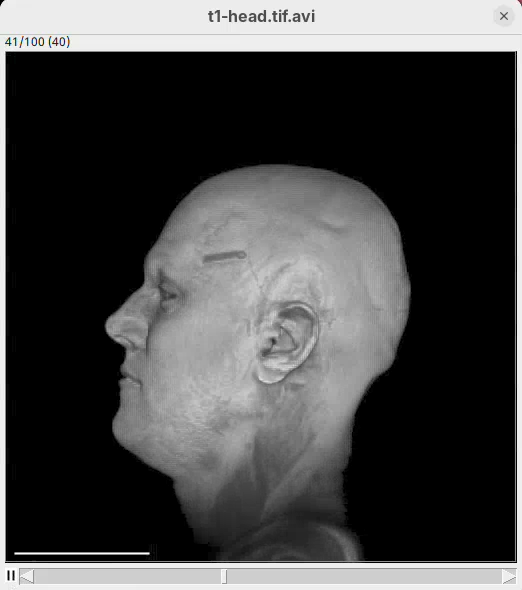

Volume Viewer

Volume Viewer is a more powerful plugin for 3D visualization as it supports slicing, projections, and rendering. The interface is interactive and intuitive to use. To open it:

- Go to

Plugins>Volume Viewer. The main interface will open in theSlicemode.

- Click around and move the sample to see optical sections from different angles.

- Then, activate the

Volumemode to render the sample’s surface in 3D and explore it as well, playing with the different rendering parameters.

Volume Viewer also provides a way to take snapshots of the current view.

3D Project

This is a simple tool to quickly generate a 3D animation (e.g., 360-degree rotation) from an image stack. There are basic parameters for adjusting the rendering, like projection method and opacity, and for controlling the animation. There’s only a bit of documentation. To try:

- Go to

Image>Stacks>3D Project...and clickOKto generate a basic animation.

As noticeable above, 3D Project doesn’t do so well with our MRI dataset. However, it works OK for fluorescent microscopy images, so I encourage you to try with other datasets in the future.